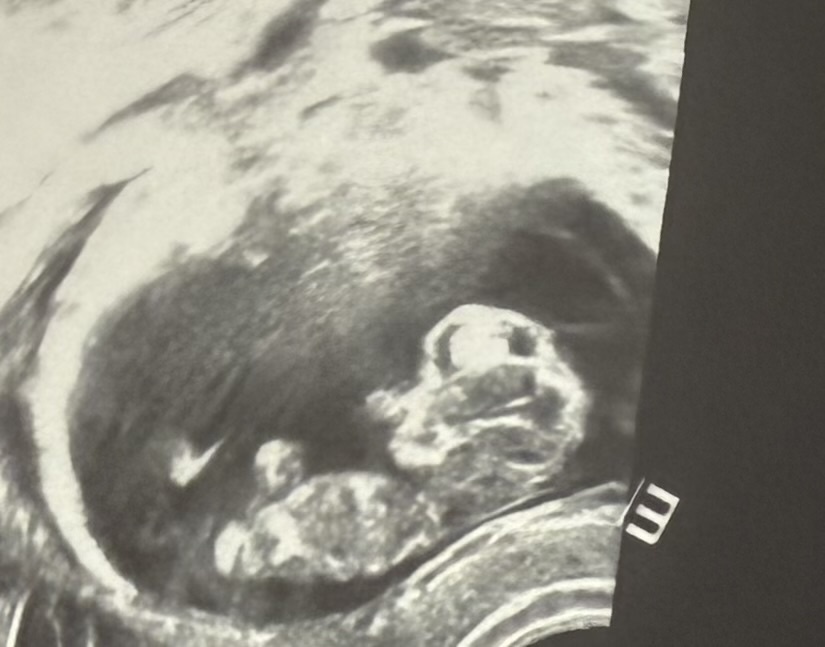

Маточная беременность 11 недель. Фото  автора.

Через месяц с небольшим Кристина повторно пришла ко мне на УЗИ.

Было уже 11 недель.